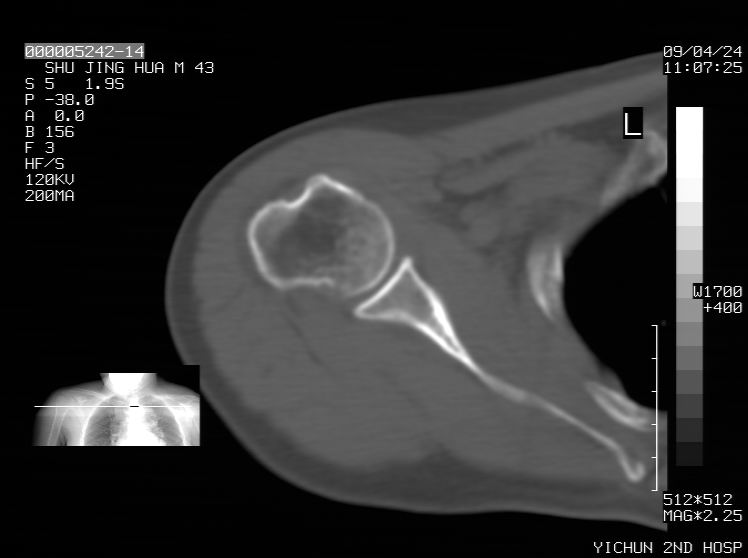

标题: CT19569:请会诊,女50岁,右肩疼痛数月 [打印本页]

标题: CT19569:请会诊,女50岁,右肩疼痛数月

钙化性肌腱炎

是指钙盐沉积在变性肌腱中的一种无菌性炎症,常见于肩关节的肩袖肌腱,引起肩部疼痛和活动受限。分为急性和慢性两种类型,急性型有肩关节突然出现急性疼痛的发作史,夜间可痛醒。

以下是引用余辉在2009-4-24 15:24:00的发言:[br]考虑钙化性肩周炎,肱二头肌长腱或相应附属组织钙化

支持